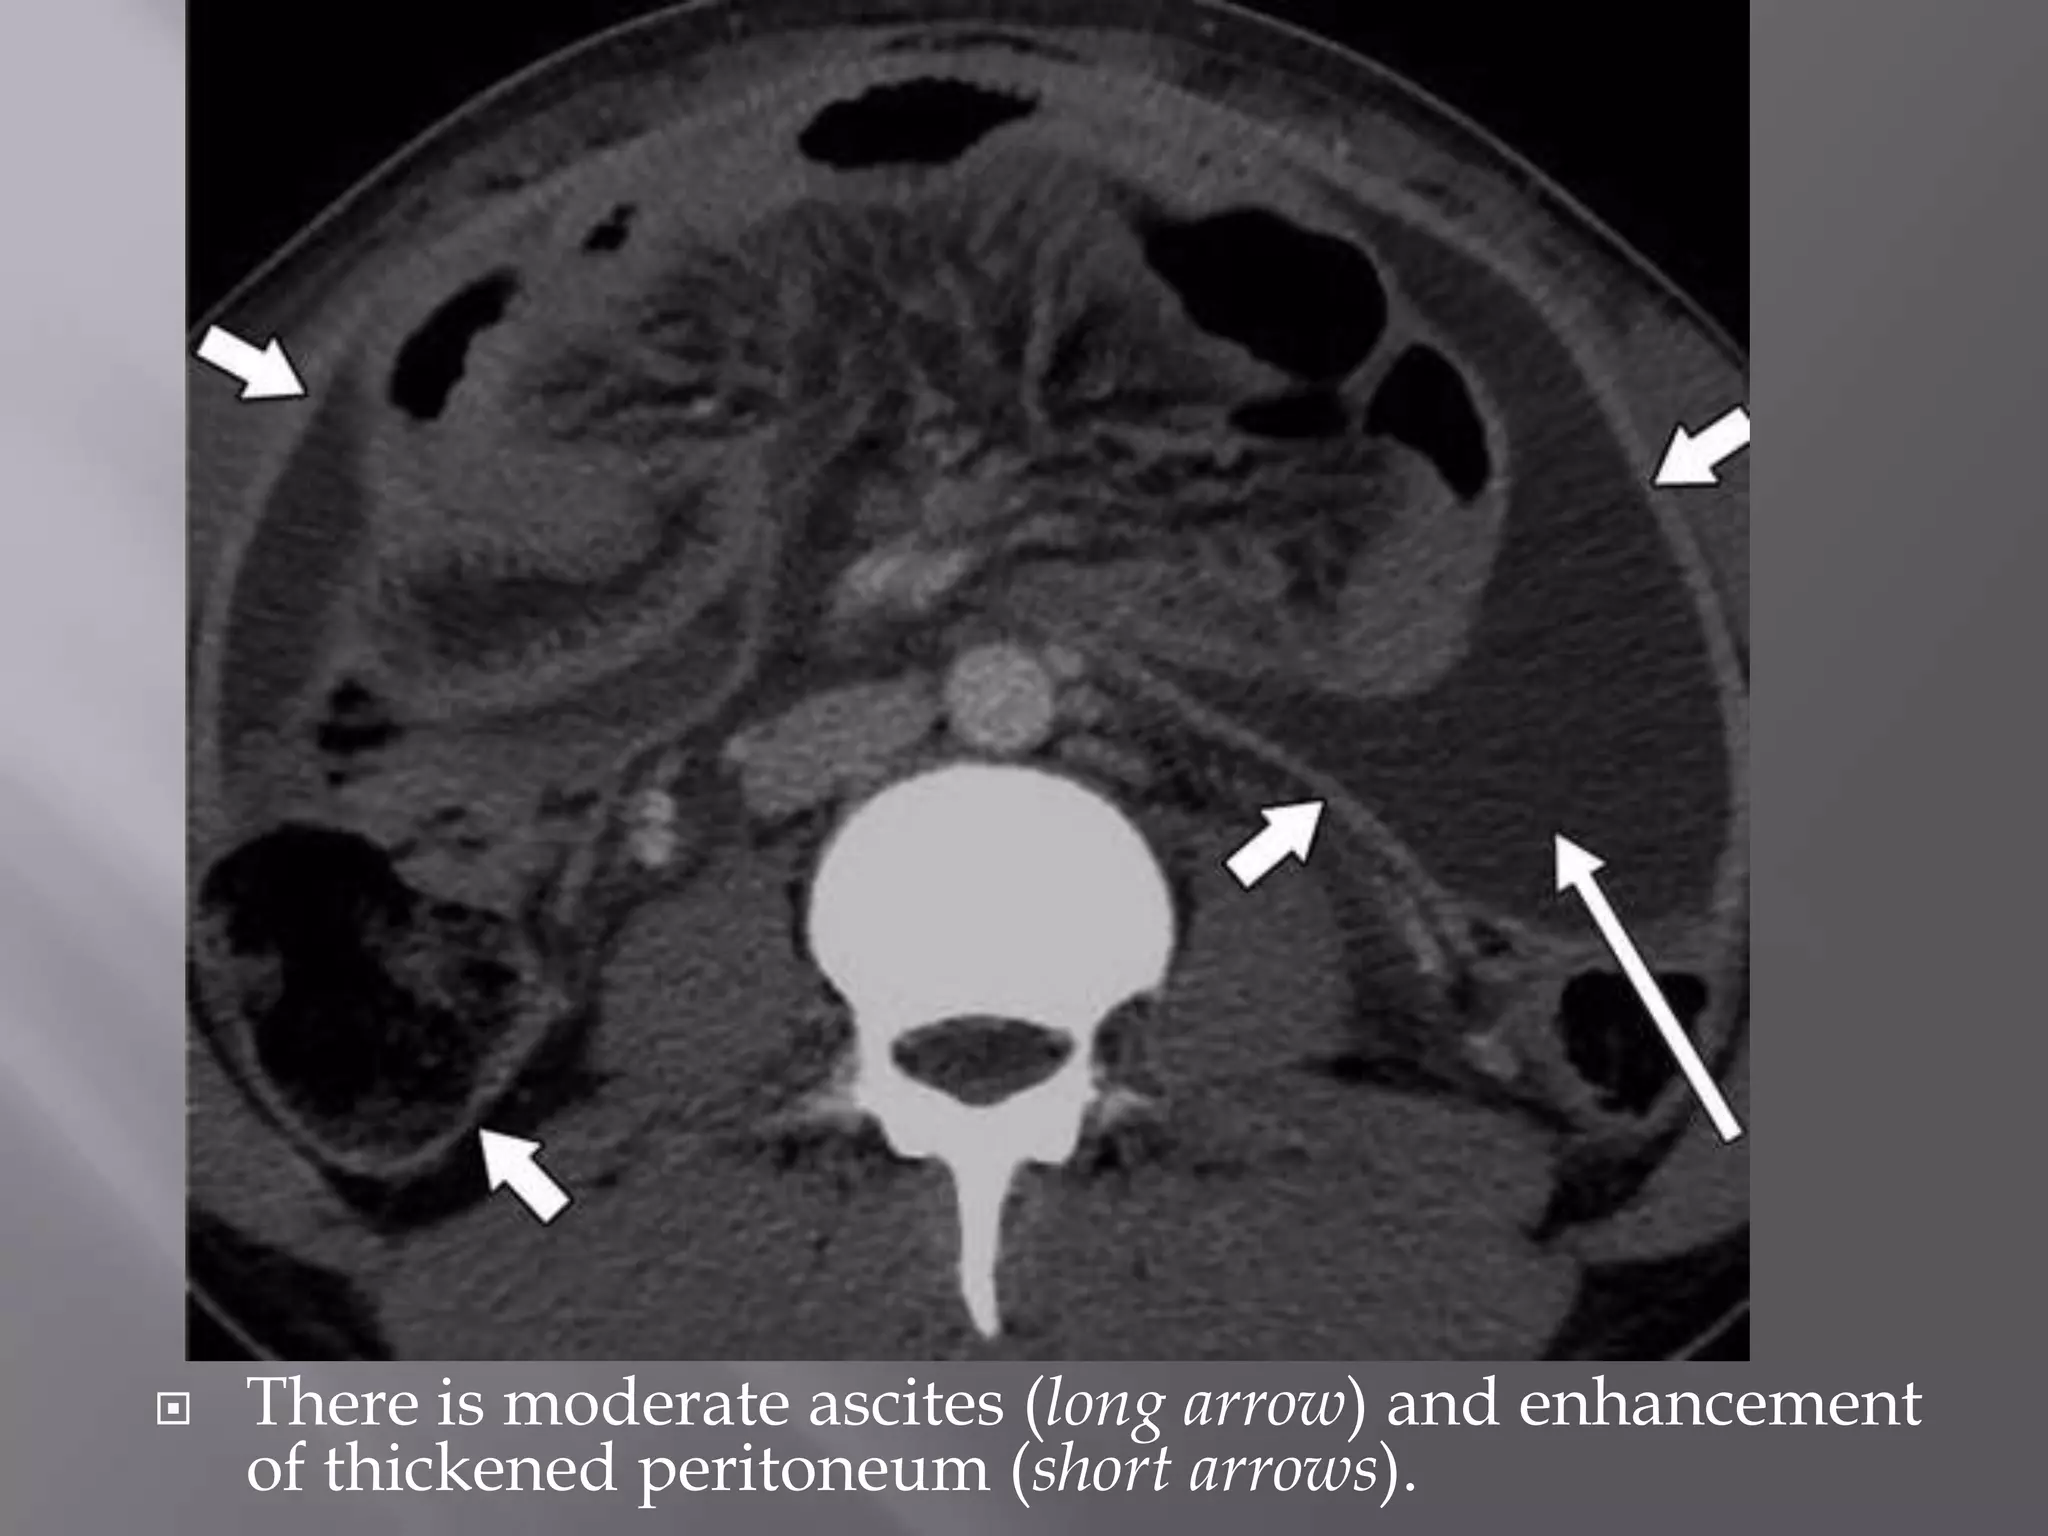

 There is moderate ascites (long arrow) and enhancement

of thickened peritoneum (short arrows).

 Peritoneal tuberculosismay affect the peritoneal cavity, mesentery, and omentum.  The most frequent form (90% of cases) is the ―wet‖ type with ascites or pockets of loculated fluid.  The ―dry‖ type is characterized by fat stranding in the mesentery, dense adhesions, and adenopathy.

 There isextensive fat stranding of greater omentum (long arrows). Peritoneum is thickened and hyperenhancing (short arrows), and pockets of fluid are present (arrowheads)

 There ismoderate ascites (long arrow) and enhancement of thickened peritoneum (short arrows).